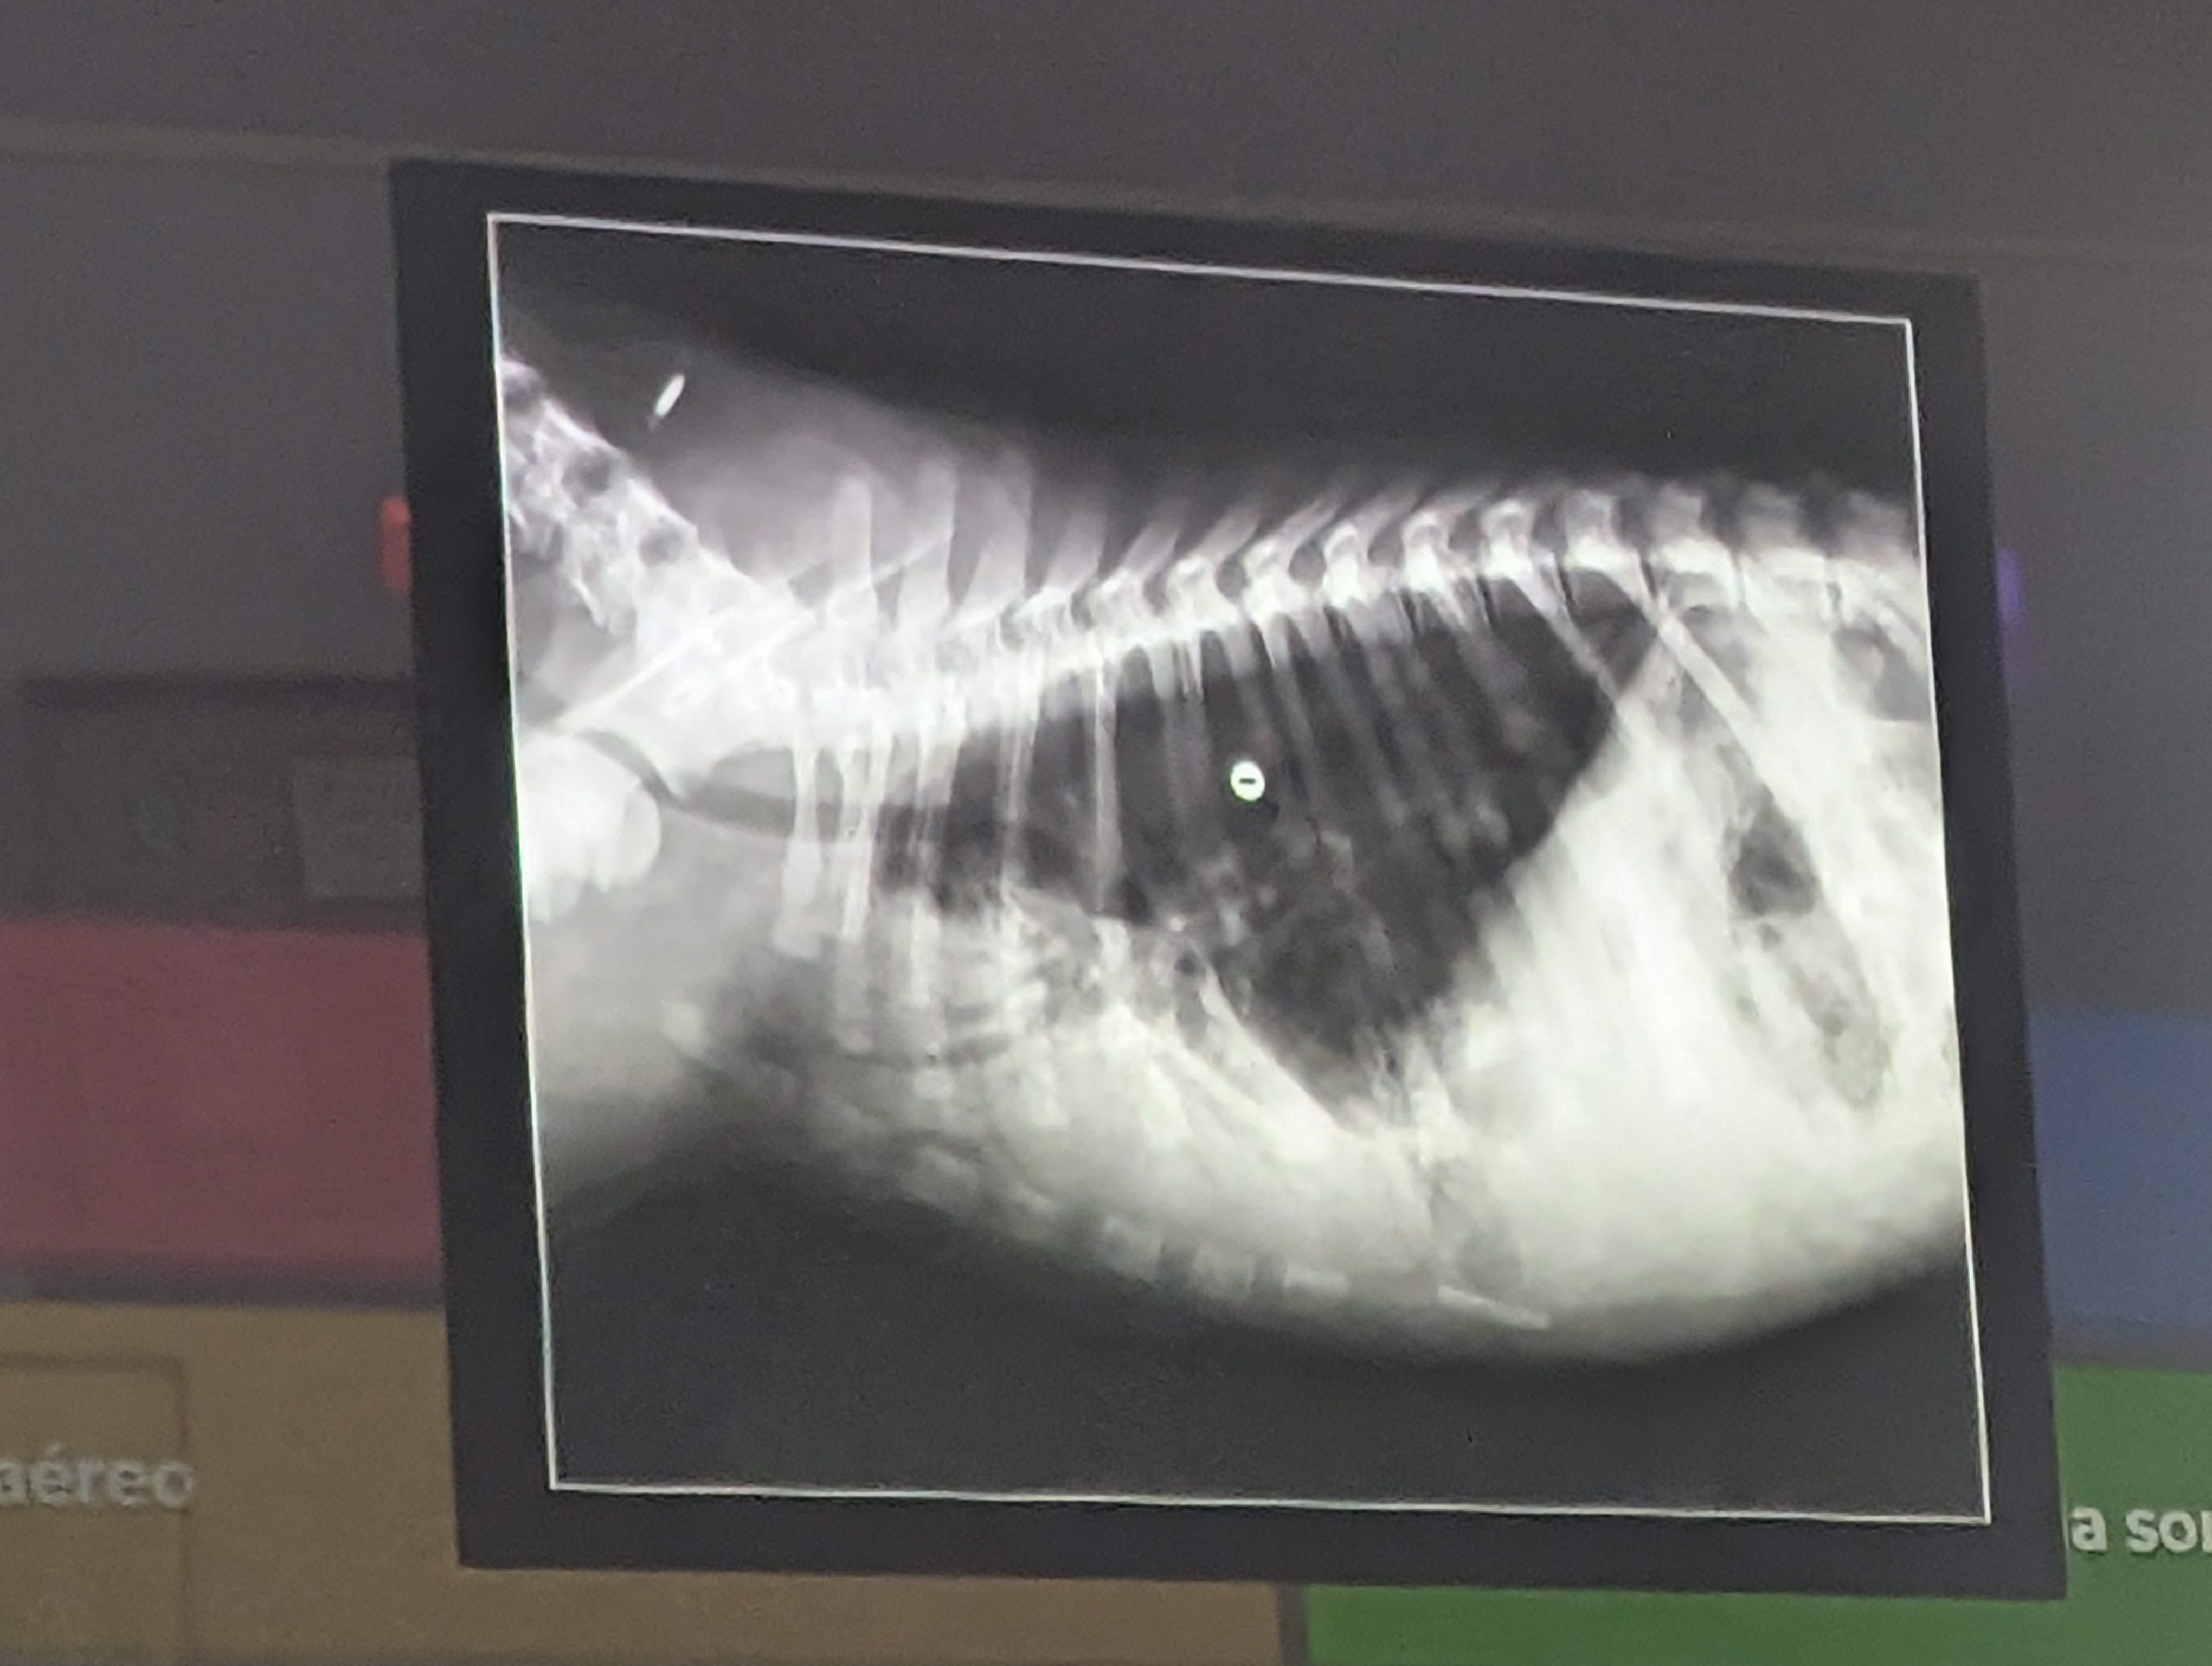

Preguna 6 - Multiple respuesta

- Hay un desplazamiento dorsal del piloro (por torsion estomacal)

- Signo de doble burbuja ( presencia de dos compartimentos llenos de gas en el estómago por el giro, el cual aparece distendido y rotado.)

- Torsión Gastrica

- Hay una dilatación gastrica (por torsión)